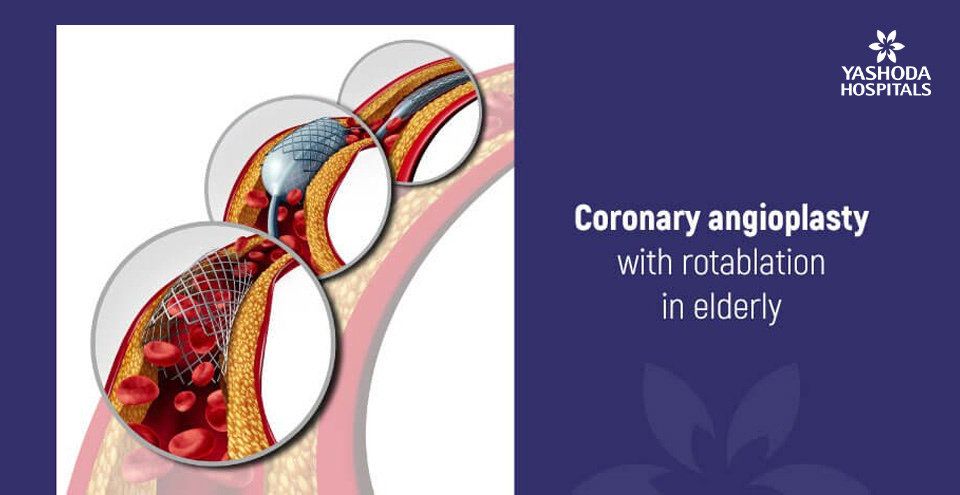

Coronary angioplasty with rotablation in elderly

Angioplasty is performed more often as it is a percutaneous procedure and a safer option to remove blockages formed in arteries [Coronary] of the heart. When the patient is above 80 years, the procedure becomes technically difficult because of age-related changes that occur in the body. As the age advances the arteries become harder due to the patho-physiological process of atherosclerosis. This process leads to deposition of calcium in the arterial wall making them harder as compared to the arteries of younger patients. The calcium deposits over the blockage from inside the lumen of the vessel and also on the outer wall of the vessel.

While the blockages in the younger individuals are easy to dilate using the balloon, owing to the softer nature of the block, it is less likely to remove the blockages with similar ease in the elderly. These blocks are relatively difficult to negotiate because of a hard matrix containing calcium and other natural salts in addition to fat. The harder blocks, which cannot be dilated using balloon before deployment of the stent due to calcium deposition, need Rotablation, an interventional tool for debulking the harder lesions.